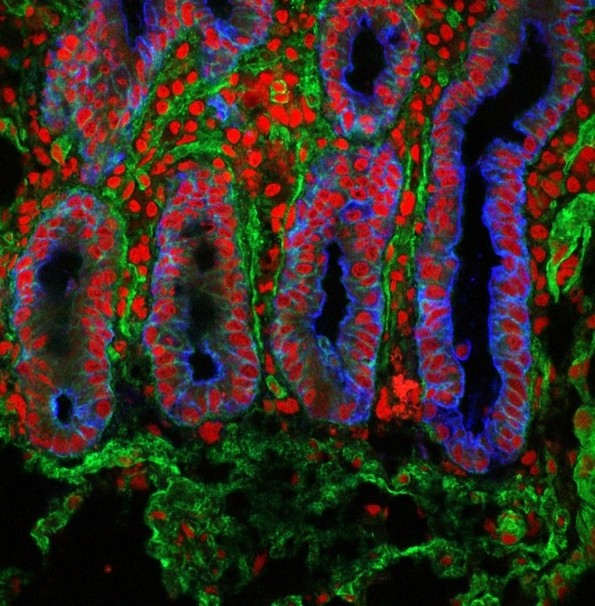

3. Тенко црево